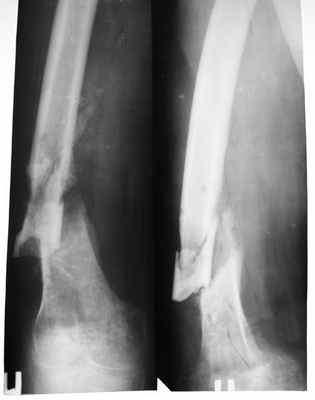

Рентгенологические признаки ложного сустава представлены:

- визуализацией линии незаращения из-за замедленной консолидации

- склерозом концов отломков

- костными наростами в области несращения (при гипертрофическом типе псевдоартроза)

- искривлением оси конечности

- смещением фрагментов

- остеопорозом (разрежением костной ткани)

Чтобы определить точно диагноз ложный сустав, клинические рекомендации называют рентген главным методом. Снимки нужно делать в прямой и боковой проекциях.

Основной признак: на рентгене отсутствует костная мозоль. Концы костных фрагментов сглажены и закруглены, полость на уровне костномозгового канала закрыта.

- гипертрофический. Концы фрагментов кости утолщены;

- атрофический. Концы фрагментов имеют коническую форму;

- истинный. Конец отломков разной формы. Один выпуклый, другой – вогнутый.